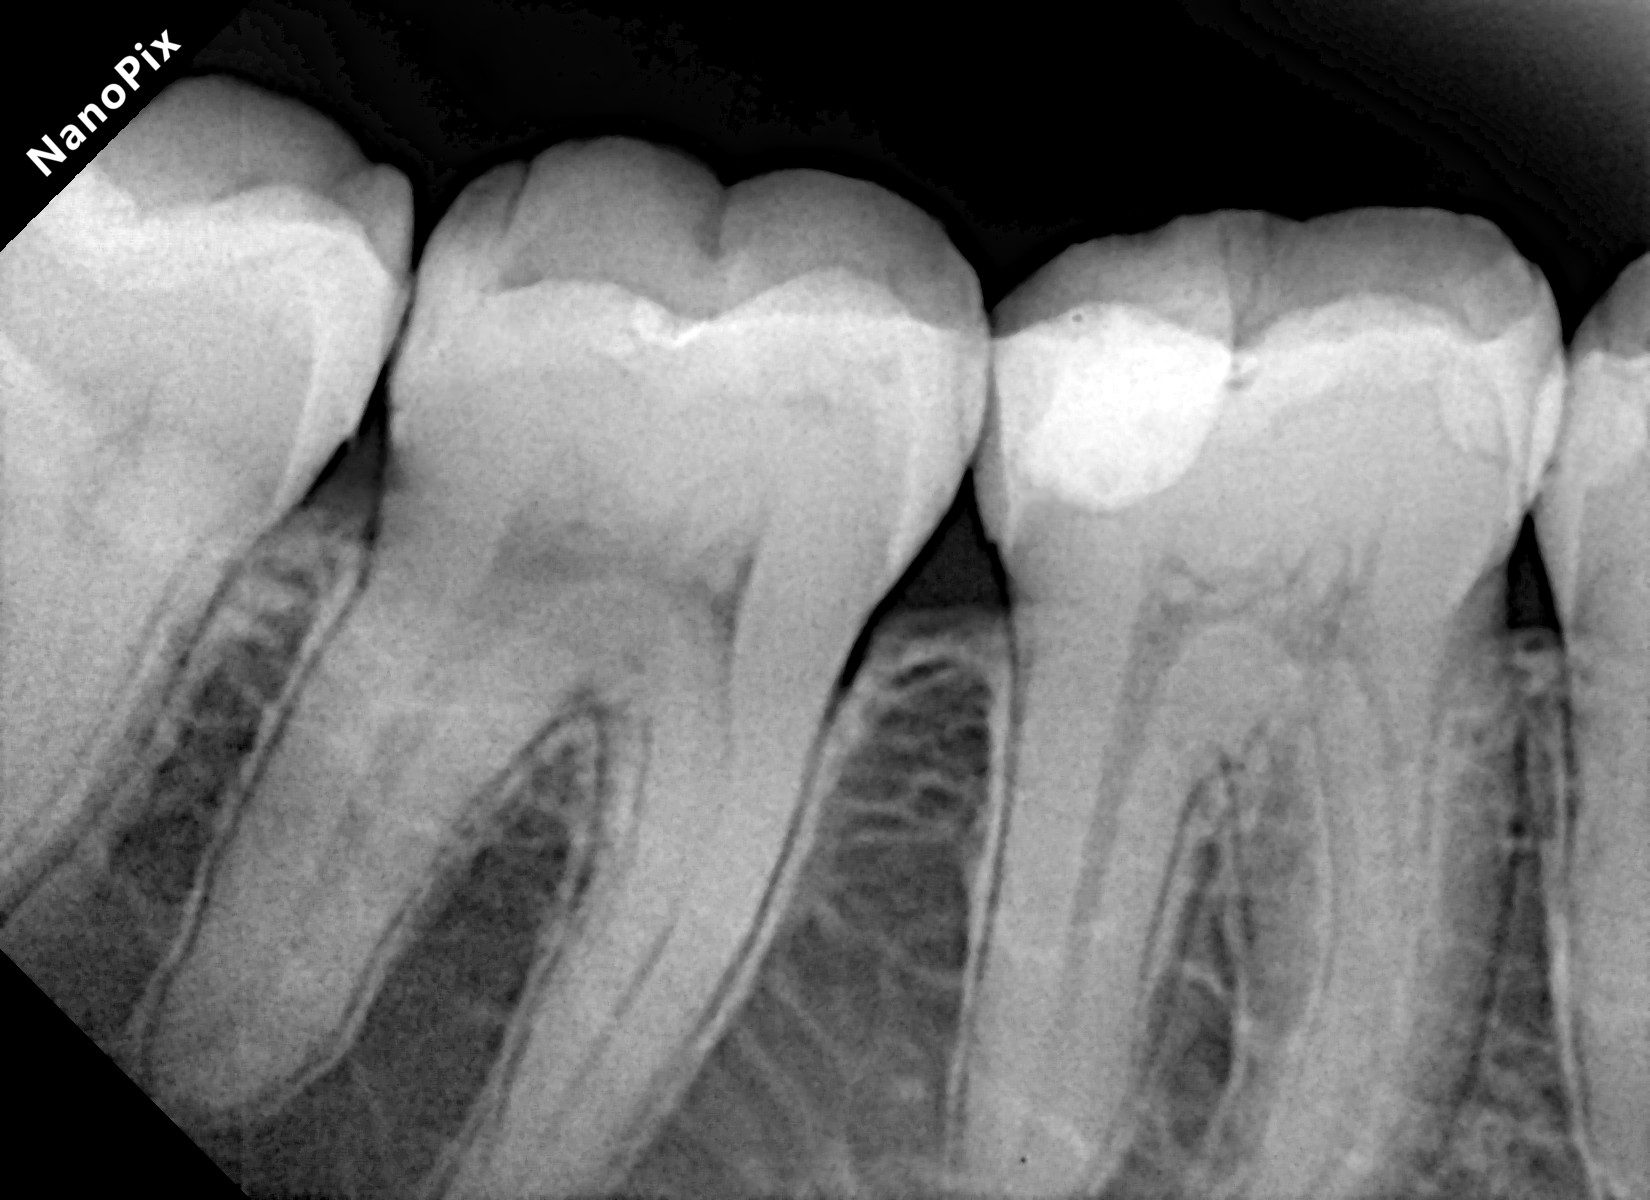

A 28-year-old woman presented to our office with complaints of sensitivity to cold temperatures and food impaction in her lower right quadrant. Her dental history revealed previous orthodontic treatment and multiple restoration failures in the same quadrant over the past 8-12 years.

Clinical examination showed significant mesio-occluso-distal (MOD) defects and Class 2 affecting teeth from #45 to #48.

Tooth #45: A distal carious lesion is suspected, potentially secondary to the adjacent mesial defect observed on tooth #46. No existing restoration is noted in this region, however, early discoloration and anatomical concavity suggest demineralization.

Tooth #46: Clinical examination revealed a mesial proximal carious defect with complete loss of the marginal ridge. On the distal aspect, an old composite restoration was observed, appearing underfilled and extended onto the occlusal surface. Evident marginal leakage and localized chipping were present along the restoration interface. Additionally, unsupported enamel was noted on the distobuccal cusp, indicating structural compromise and the risk of cusp fracture.

Tooth #47: An existing occlusal composite restoration demonstrated marginal discoloration and leakage. The distal surface exhibited a composite material of a different shade and texture, suggestive of a restoration placed at a later date. Lack of a defined marginal ridge resulted in an improper proximal contact. On the mesial surface, dark discoloration contiguous with the existing mesial pit composite indicated the presence of a recurrent or active Class II carious lesion.

Tooth #48: The mesial aspect showed dark discoloration extending into the existing mesial pit composite restoration, consistent with a developing or recurrent Class II carious lesion.

Bitewing radiograph confirmed the presence of multiple MOD / Class II carious lesions corresponding to the clinical findings. None of the defects demonstrated radiographic proximity to the pulp.

Figure 1. Multiple defects starting from tooth #45 to #48 as described above.Figure 2. Multiple class 2 defects starting from tooth #45 to #48 with loss of ideal contacts and contours.